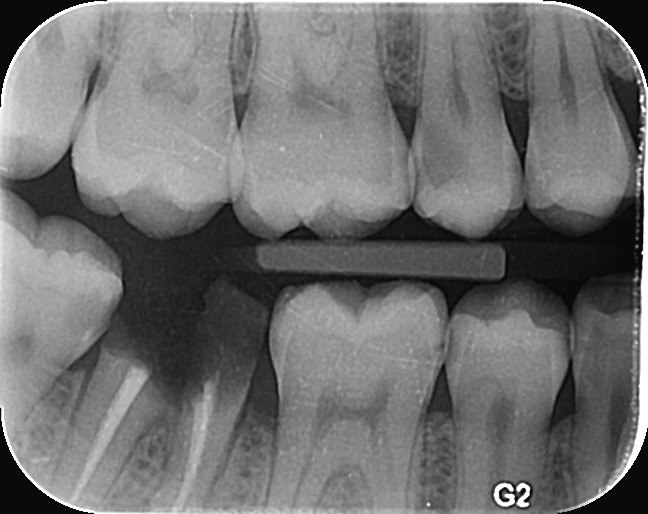

1. Which surfaces shows dental caries?